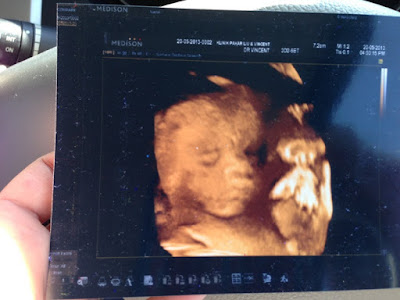

walau apa cara sekalipun doc kena capture even sekeping jadi le scan 3D

Memula tu baby malu nak tayang muka

Asik la dok tutup muka

Hampir putus asa dah ni lalalala

Tetiba akhirnya....

Subhanallah kagum aku masa doc tunjuk 3D ni

Doc ada cakap berat baby 782g ke 752g cenggitu la

"Kan kakak dah cakap baby girlllll"

Ayat kemenangan najlaa

Huhuhu mama dgn papa ingatkan baby boy pasal lasak semacam

Takpelah jantina ape sekalioun janji baby sihat alhamdulillah